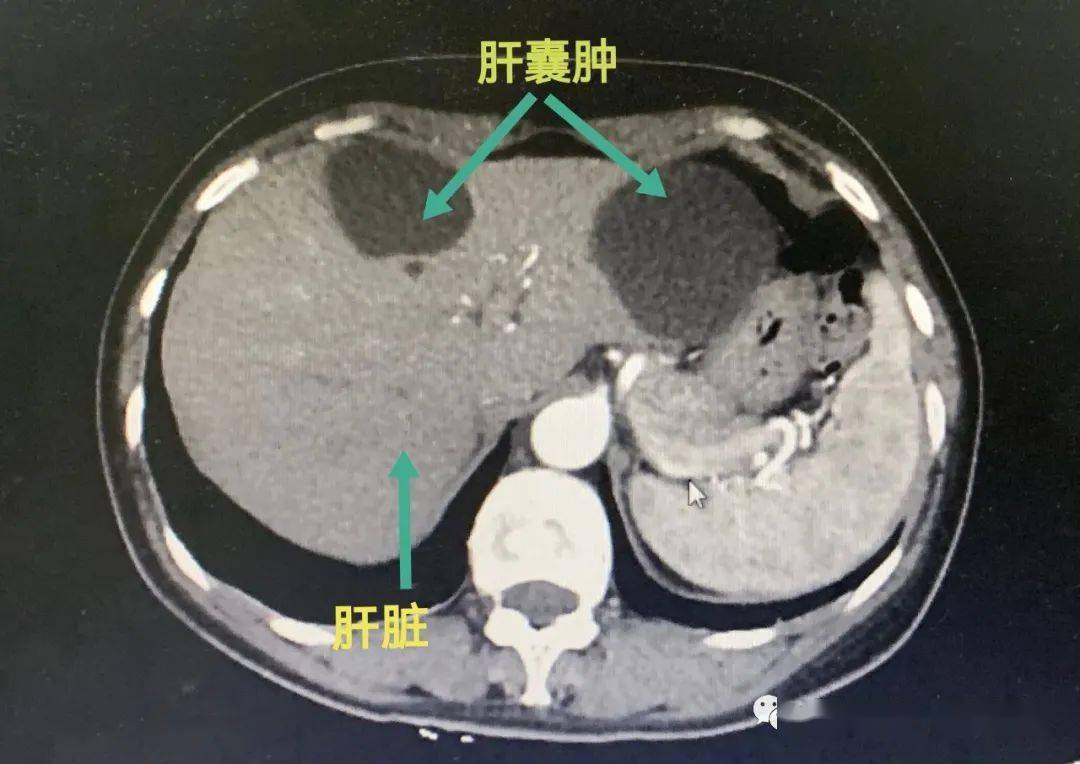

肝囊肿是一种较为常见的肝脏良性疾病,通常情况下不严重,但特殊情况需重视具体说明如下多数肝囊肿患者无明显症状,小囊肿通常不影响健康肝囊肿指肝脏内出现的囊性病变,多数患者因体检发现当囊肿较小时,一般不会对肝脏功能及身体健康造成明显影响,无需特殊治疗,只需定期通过超声或CT检查监测囊肿。

肝囊肿是一种常见的肝脏良性疾病,通常不会恶变,多数患者无明显症状,常在体检时偶然发现其病因可分为两类1 病因先天性因素主要与胚胎时期胆管发育异常有关,导致胆管闭锁或扩张,形成囊性结构后天性因素包括炎症如胆管炎创伤如腹部手术或外伤寄生虫感染如肝包虫病等,这些因素。